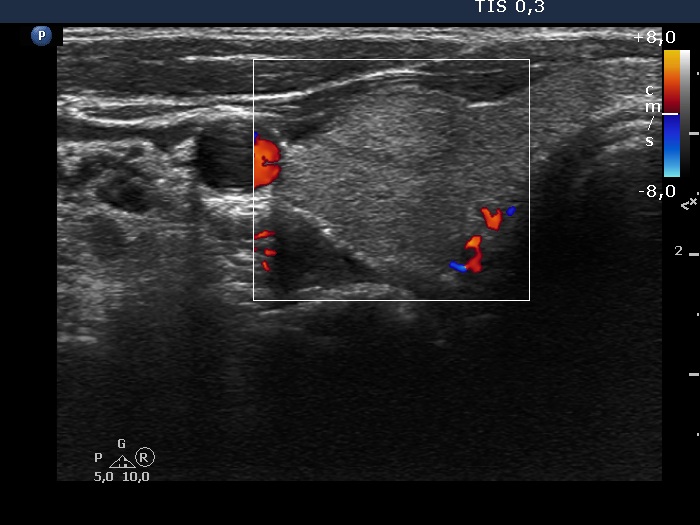

Right lobe, longitudinal scan

Right lobe, transverse scan, color Doppler mode. The ventral echonormal nodule is avascular.